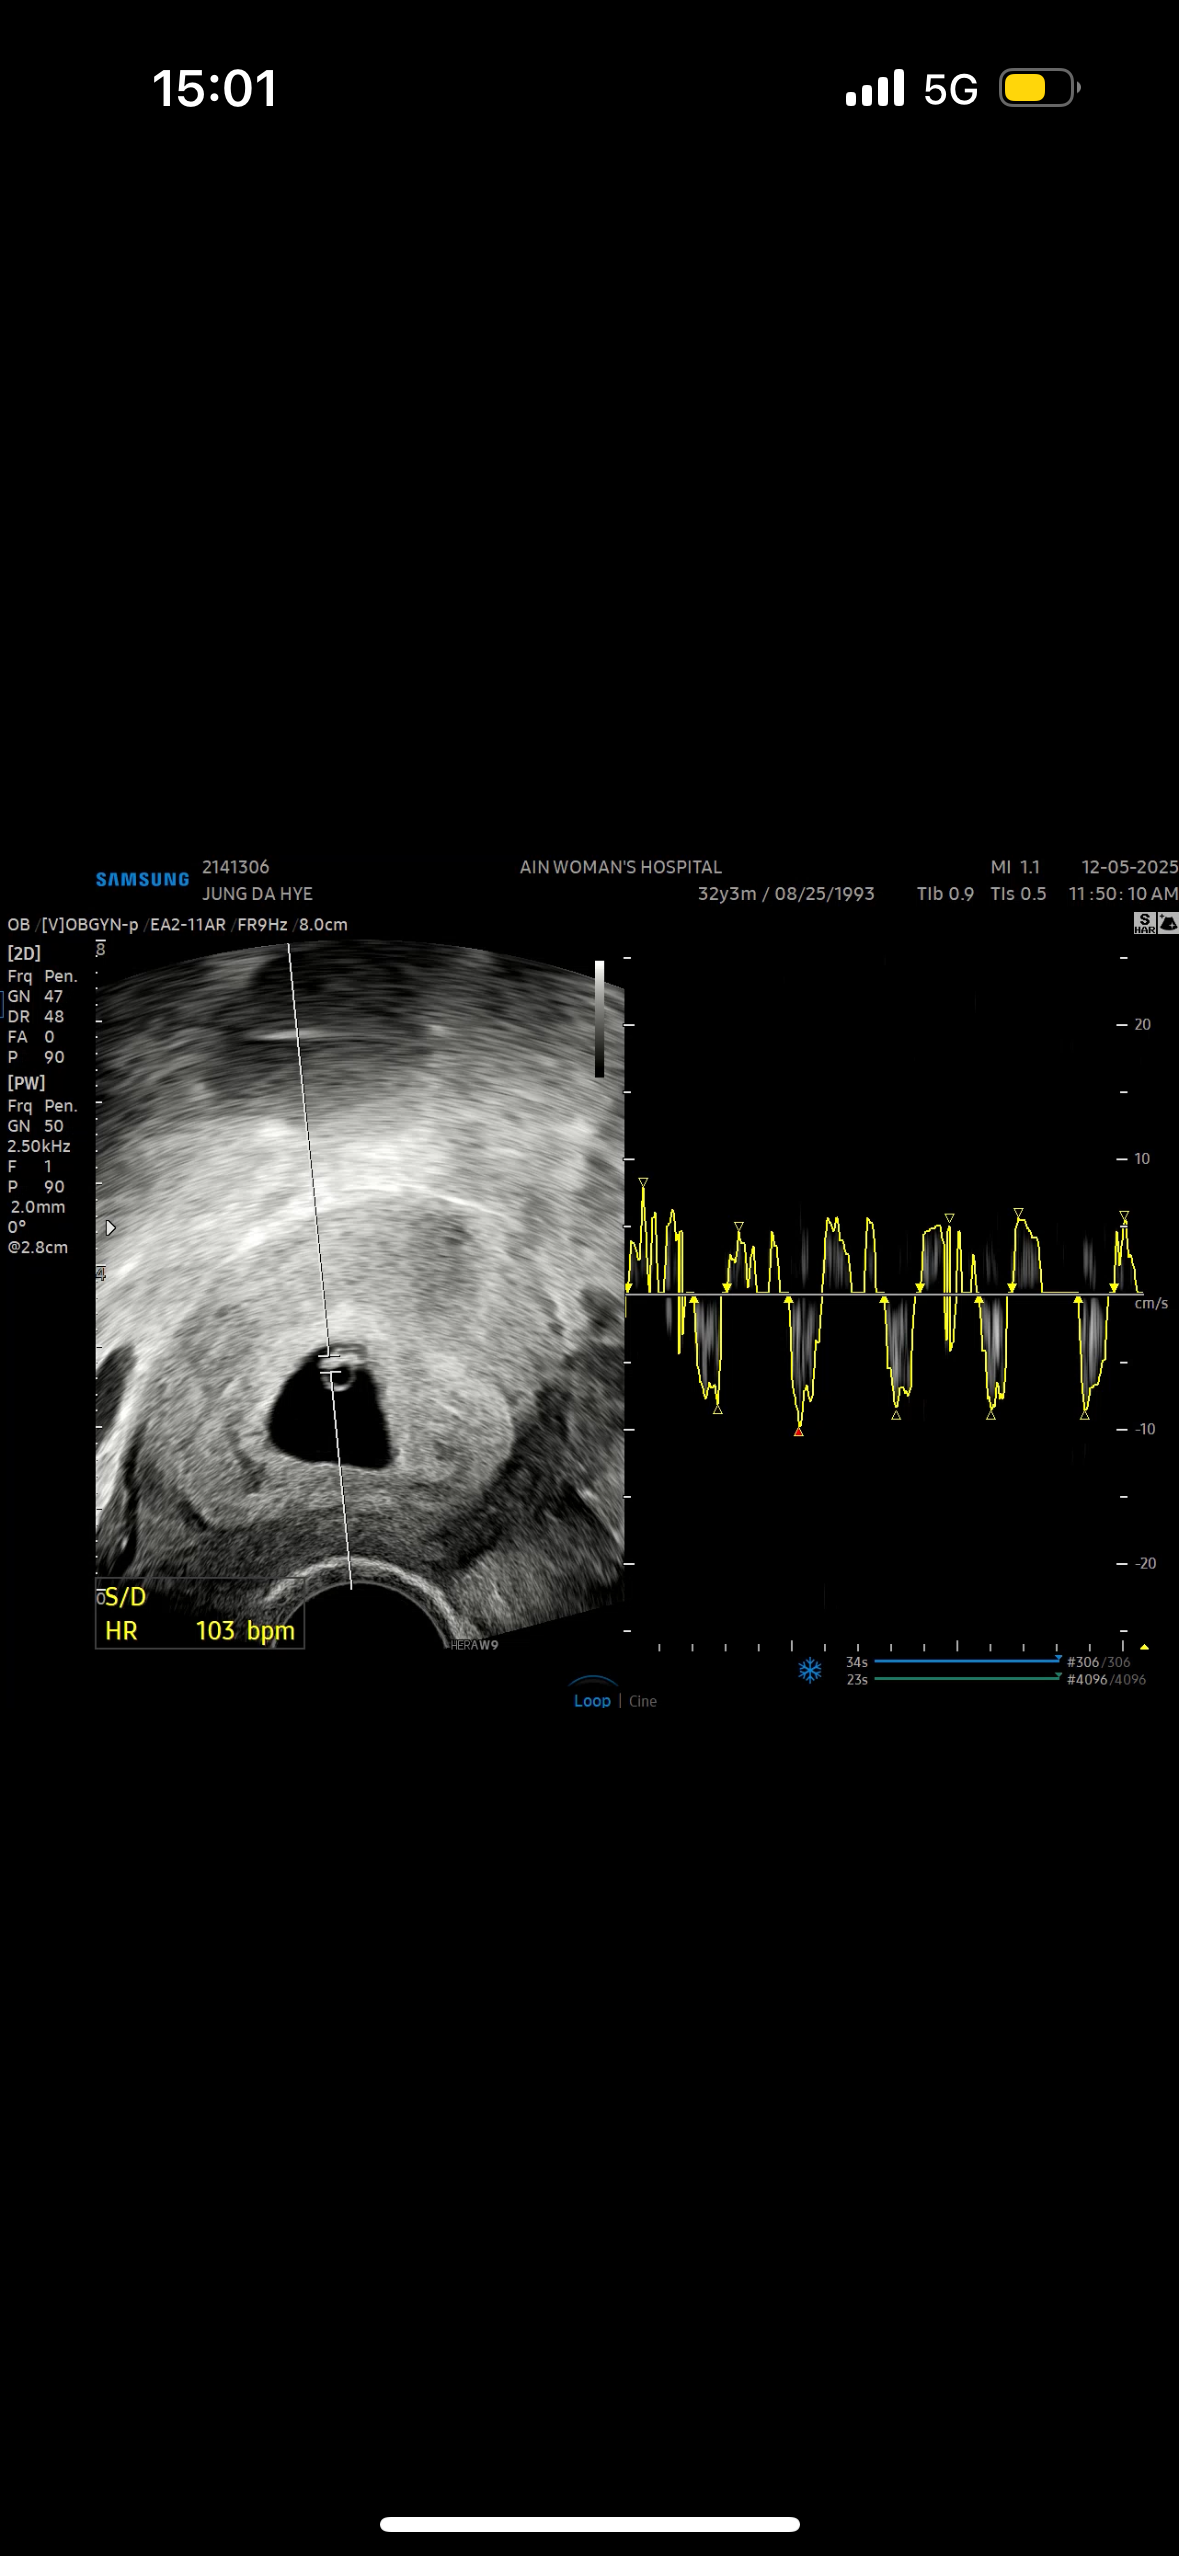

마지막 생리기준 5주 4일차라서 난황만 생각하고 갔늨데 애기도 작게 보이고 심장소리도 작지만 들려서 듣고왔어요 ㅠㅠㅠ 너무 신기👼❤️

선생님이 들릴수도 있을거같다고 하면서 좀 찾아주시더니 작게 들리더라구요!! 100넘게 뛰고있다고 했어요 주차로 하면 6주차 되어보인다고 하셨어요!